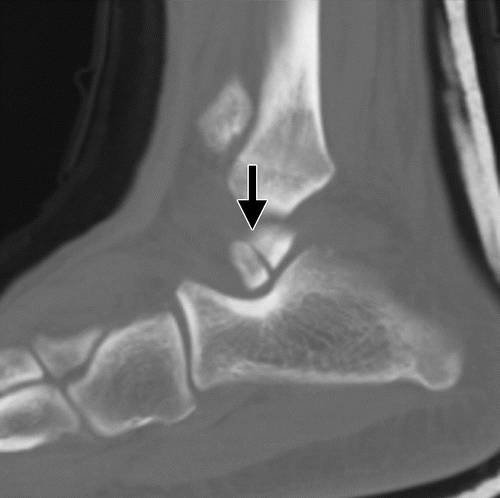

这种损伤必须与三角骨 - 一个附件后骨小梁区分开来。 在放射照相术中,后过程的断裂显示不规则的边缘(图13),而三角骨是圆形或椭圆形,具有光滑的皮质边缘(图14)。 双侧X线照片的价值有限,因为据报道三分之二的病例是双侧的(32)。 如果射线照片不确定,应进行CT。

图13b后突骨折。 (a)右足的外侧X光片显示在距骨后方的小骨质碎片(箭头)。 (b)右脚的轴向CT图像显示后路过程骨折(箭头)以及粉碎的程度和程度。

图14 三角骨。 踝部的侧面X线片显示在距骨后方的椭圆形皮质骨化(箭头)。